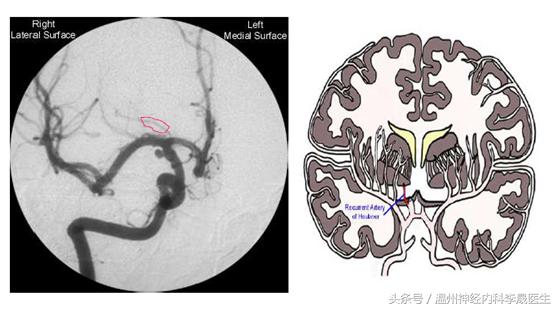

首先看看前动脉的供血区域,左图红色,右图绿色区域就是大脑前动脉的供血区域

1)反支(Heubner动脉)

(一)大脑前动脉在前交通与Heubner返动脉之间闭塞